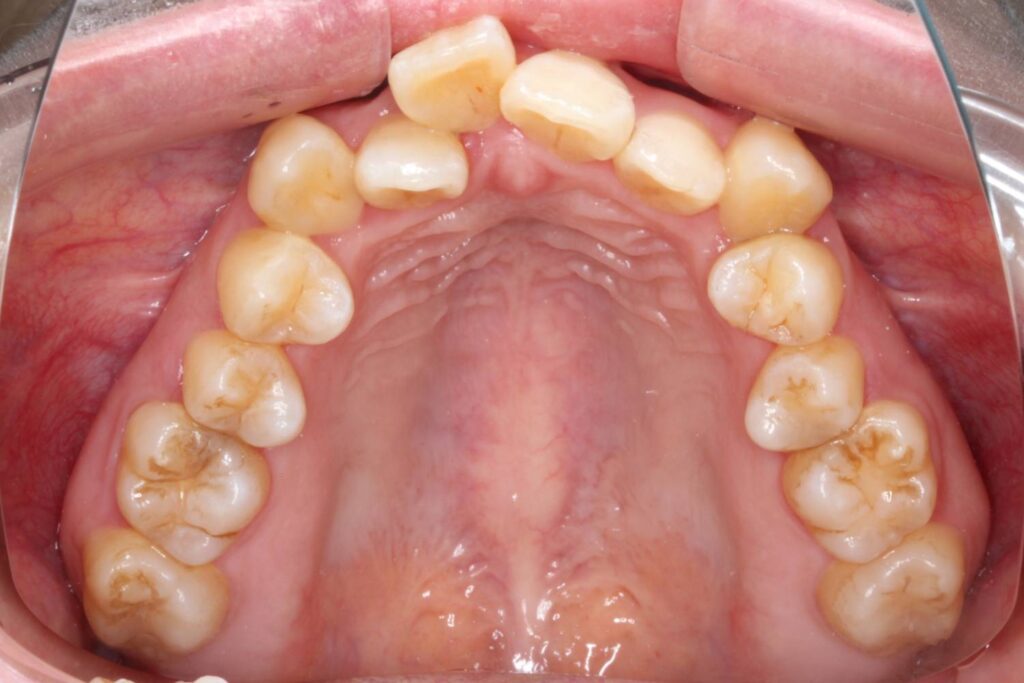

噛み合わせが大きくずれていることから、上顎両側4番を抜歯させていただきました。

下顎は非抜歯で、IPRと言って歯と歯の間をわずかに削る処置を行うことで歯が並ぶスペースを確保しています。

After

治療後は上顎の前歯が引っ込み、歯のがたつきも改善しています。